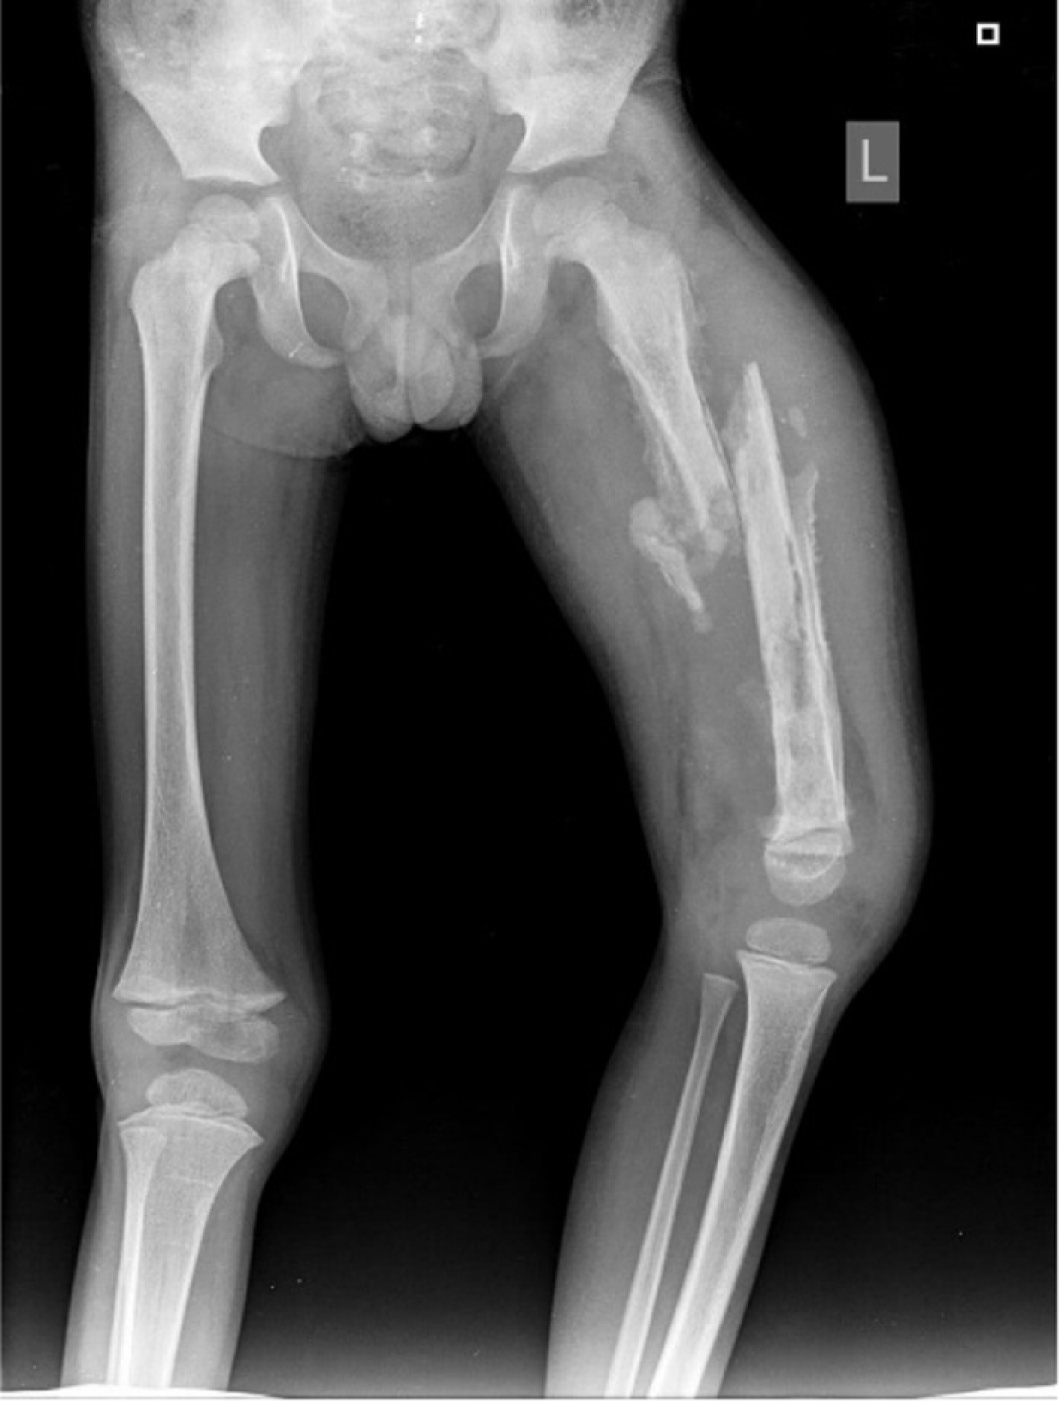

However, the amount of osteomyelitis and septic arthritis I observed in children at Tenwek could not simply be explained by the increased incidence of trauma. The incidence of pyogenic acute hematogenous osteomyelitis in LMICs is reported as 43-200 cases/100,000. Whereas the incidence of acute hematogenous osteomyelitis in Western countries is reported as 1-12 cases/100,000.16–18 With delayed presentations, children often presented with bone abscesses or even evidence of chronic osteomyelitis with draining sinus tract. Additionally, distinguishing chronic pyogenic infections from extrapulmonary tuberculosis (Figure 3) often is a diagnostic dilemma. One of the hardest, but frequent, scenarios we came across, were children with chronic osteomyelitis that developed a pathologic fracture (Figure 4). In this situation, we needed to try to treat the chronic infection, but also achieve bone healing. Without infectious disease doctors and peripherally inserted central catheters, the medical management of both acute and chronic osteomyelitis can be challenging.

Figure 4. Radiograph of a 5-year-old boy with pathologic fracture of his left femur chronic osteomyelitis.